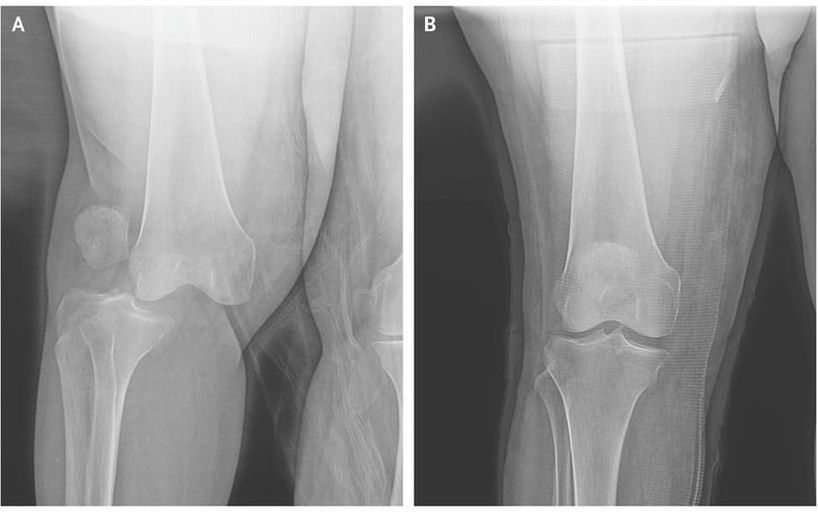

A 76-year-old woman with obesity presented to the emergency department after being struck by a motor vehicle while walking to the store. She was awake and reported that her knee “bent the wrong way” as the vehicle hit her. Trauma evaluation revealed no intrathoracic or intraabdominal injuries. She had severe pain in the right knee but had preserved distal pulses and sensation. Anteroposterior radiographs showed lateral dislocation of the right knee (Panel A). A feared complication of this injury is damage to the popliteal artery, which can result in ischemia and, in some cases, lead to amputation. Lateral dislocations can result in disruption of the anterior and posterior cruciate and medial collateral ligaments and are associated with peroneal nerve injury. After the patient received conscious sedation with ketamine, bedside knee reduction was performed (Panel B). The patient had no neurovascular injury. She underwent external fixation of the knee and repair of the knee ligaments and was discharged to a skilled nursing facility on hospital day 9.